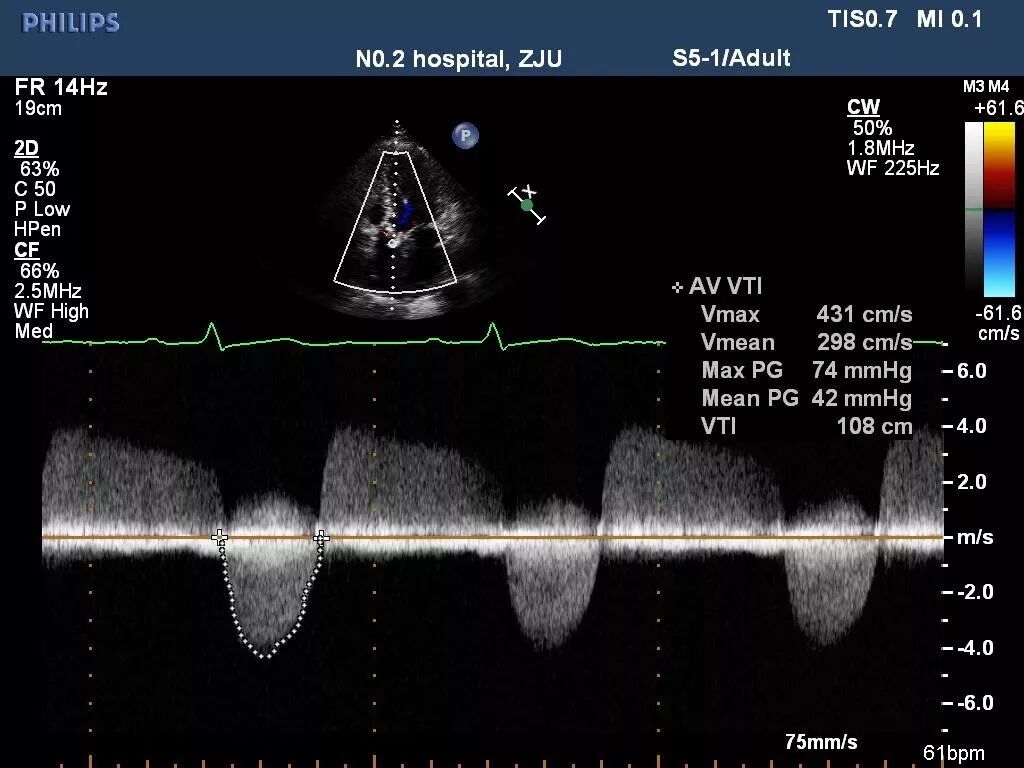

TTE确认AS严重性

● LVEF: 30%

● LA 5.47 cm LVEDd 6.05 cm

● Severe aortic stenosis

▷ AVA: 0.52 cm2

▷ Vmax: 4.3 m/s

▷ Mean gradient: 42 mm Hg

● Mild AR

Figure 1

TTE评估

来自浙江大学医学院附属第二医院的余蕾医师分享了超声方面的临床经验,心脏超声评估主要包括三个方面的内容,首先,对心脏瓣膜整体形态结构等进行测量,对主动脉瓣形态结构进行评价,判断是否为二叶式主动脉瓣畸形、测量瓣叶厚度、钙化部分是否均匀等。

其次,测量有效瓣口面积、最大跨瓣流速、平均跨瓣压差等进行评估瓣膜狭窄程度,通过放大模式清晰显示主动脉瓣结构,再通过血流动力学观察、判断主动脉瓣反流程度。

最后,对心脏整体功能进行评价,判断心功能,观察二尖瓣和三尖瓣的血流动力学,判断是否存在狭窄、反流,以及狭窄和反流的程度。另外,需评价心脏是否存在心包积液、肺动脉高压。